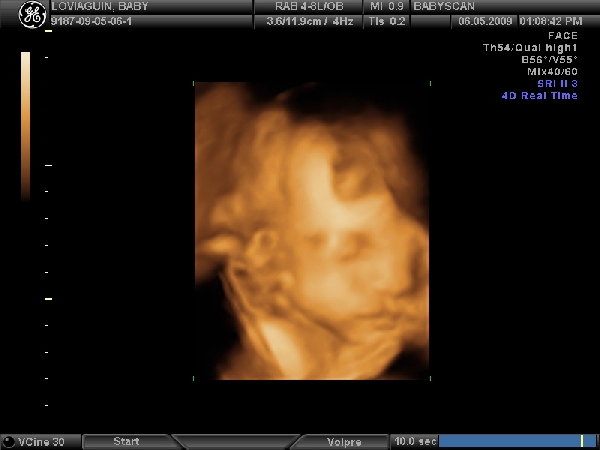

Nemsokara keszulok 3d-re!!!!Delutan 1/2 2-re kell menni,remelem most ezek jobban odafigyelnek majd,mert az elozo,ahol a 21.heten voltunk,na az katasztrofa volt....unott csaj,folyamatos basztatas hogy meg kicsi,ennek igy semmi ertelme... :shock: :evil:

Ezeknel mar voltam a 12.hetin,es a genetikai uh-n,es rendesek,turelmesek,kedvesek voltak.

Na es akkor...!

Megvolt az uh,edes kis lanykat novesztgetek pocakomban.Kisse szegyenlosnek mutatkozott,az istenert sem akarta a kezet elvenni az arca elol,sot kesobb a masik kezevel is fogta a fejet...es egy lab is bejatszott a kepbe :lol: :lol: :lol:

Kaptunk vagy 40db.kepet 8) lattuk minden porcikajat!Vegre a ket szemunkel a nuncijat is :lol: !Turelmes,rendes,kedves dokineni csinalta....elegedett vagyok apaval egyutt.Sikerult megint elpityerednem,persze a buszke apuka is csak amuldozott a lanyan!!!

Mereteink:

BDP(fejatmero):7,56cm

HC(fejkorfogat):28,0cm

AC(haskorfog.):26,78cm

FL(combcsont):5,96cm

HL(felkarcsont):5,49cm

becsult suly:1654gr.

Szoval teljesen rendben vagyunk,remenykedtem hogy nem produkalunk orias mereteket,mindenki riogat a hasmeretem alapjan....jo lenne ha nem lenne egy benga orias bebi :lol: :lol: 8)

Meretek alapjan julius 8 koruli a szuletesi ido.De nem modositok,jo ez igy ez a tol-ig idopont...